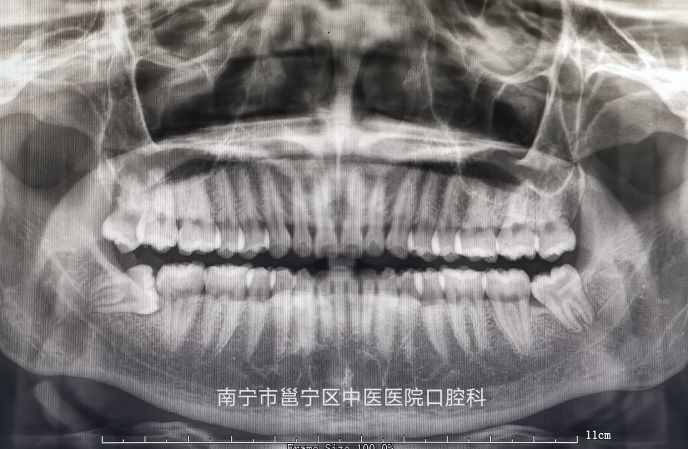

一张全景牙片 发现大问题 口腔曲面断层X线摄影是通过专门设计的口腔曲面全景摄影X线机,将上颌骨、下颌骨、颞颌关节、上颌窦、鼻腔及全口牙齿的影像同时显示在1张体层照片上的摄...